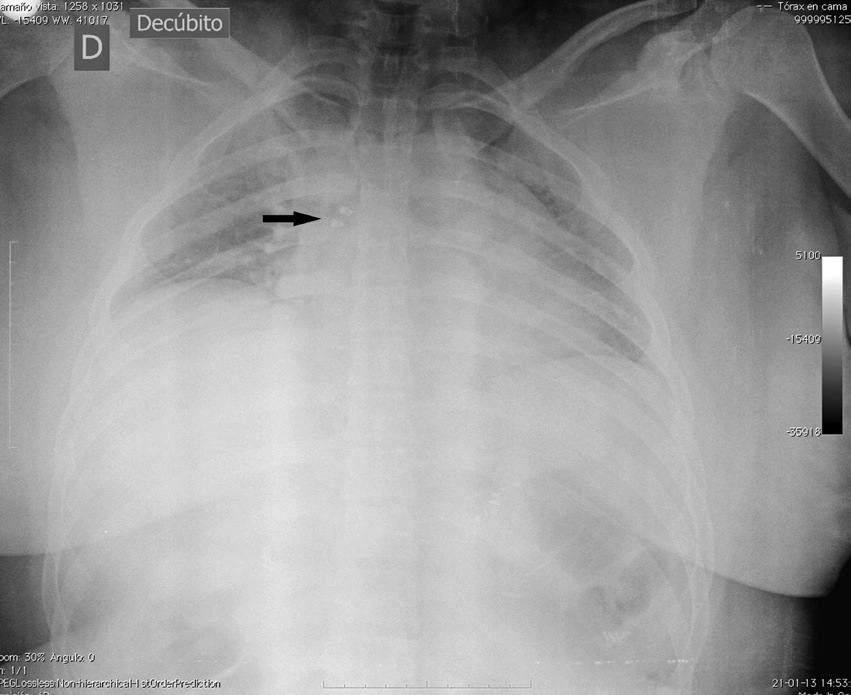

En el postoperatorio inmediato la paciente acusa la ausencia de prótesis transitoria de incisivo central superior izquierdo. (Figura 1). Se realiza radiografía de tórax y abdomen simple, que revela presencia de cuerpo extraño en bronquio fuente derecho. (Figura 2). La prótesis es removida sin complicaciones mediante fibrobroncoscopia a las 8 h del post-operatorio bajo anestesia general.

Figura 2 Radiografía de tórax en decubi.